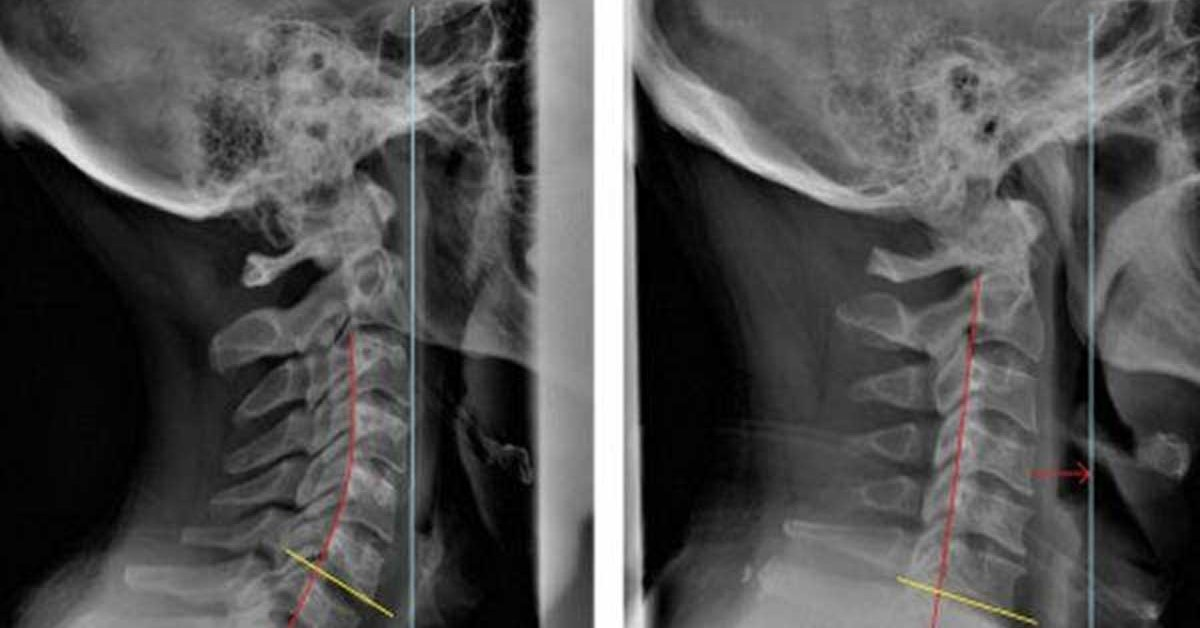

- Chụp X-quang xương gót bên và trục: Phương pháp này cung cấp và giúp quan sát hình ảnh bàn chân và xương chân, có thể phát hiện vôi hóa ở phần gần của điểm bám gân hoặc các điểm lồi xương ở phần trên của xương gót. Tuy chụp X-quang không cho hình ảnh của gân nhưng rất hữu ích trong việc loại trừ các khối u xương bệnh lý.